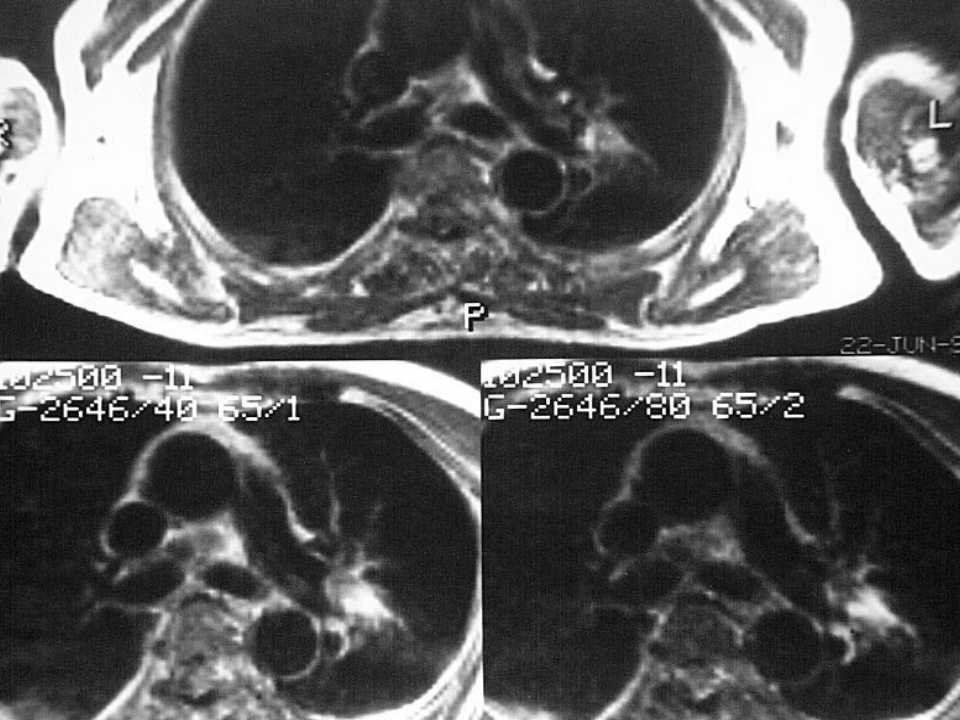

肺癌影像诊断